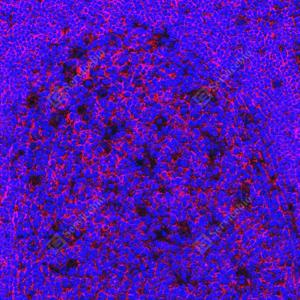

IF检测CD19蛋白(货号 GB12006)(红色). 样品: 人扁桃体, 4%多聚甲醛 (货号G1101) 固定12-24小时. 抗原修复: 柠檬酸抗原修复液(干粉, pH 6.0) (G1201), 高压锅均匀喷气计时2分钟. 封闭: 3% BSA(货号GC305010)的PBS溶液, 室温孵育30分钟. —抗: 1: 500稀释, 4℃ 孵育过夜. 二抗: Cy3标记山羊抗小鼠IgG (H+L) (货号GB21301), 1: 300稀释, 室温孵育1小时. |